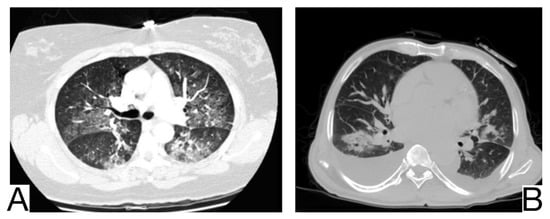

Viral pneumonia is defined as a diverse entity, and it is mainly the current epidemic context that suggests the origin of COVID-19. The treatment proved to be similar at present []. Radiological characteristics in differential diagnosis: preferential central-parenchymal involvement (Influenza type A, Adenovirus, Hantavirus) (Figure 6A); additional findings, such as centrolobular nodules and bronchial wall thickening (RSV, MERS, Influenza type A); coexisting pulmonary edema (Hantavirus); pleural effusions (RSV, MERS); hilomediastinal lymphadenomegaly (Influenzae type A) [,,].

Figure 6. (A). Multifocal areas of poorly defined focal consolidation in a patient positive for influenza A (H1N1) (B). Bilateral ground-glass opacities and dense airspace consolidations in a patient with Pneumocystis jirovecii pneumonia (C). Halo sign in a patient with aspergillosis. Note. Adapted from Elmokadem et al. (2021) [] (A), Sullivan et al. [] (2020) (B), and Dr. Laughlin Dawes (C).

10.3. Pneumocystis Pneumonia

Pneumocystis pneumonia is an opportunistic fungal infection that mainly affects immunodeficient patients affected by AIDS or undergoing immunosuppressive therapy (Figure 6B) []. History and laboratory tests are helpful but often insufficient for a differential diagnosis of COVID-19 pneumonia [,,].

Imagistic diagnosis characteristics are symmetrical, centroparenchymal and perihilar, ground-glass, confluent opacities, generally with subpleural reduction, a predilection for the upper lobes, sometimes cobblestone appearance; pneumatoceles [,].

10.4. Aspergillosis

It is caused by Aspergillus Fumigatus and generally affects immunocompromised patients with severe neutropenia. Radiological diagnosis highlights: ground glass opacities and cobblestone aspect are not typical and do not precede condensations, which frequently show a surrounding halo of ground glass (halo sign) [] (Figure 6C).

In case of consolidations without ground glass halo and the absence of other ground glass opacities, COVID-19 pneumonia is unlikely; lymphadenopathy and pleural effusions are also present.